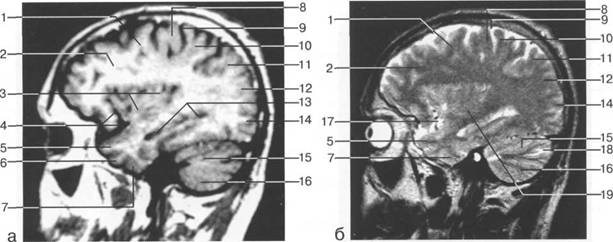

В латеральных отделах дно передней череп 13513u2010n 85;ой ямки образовано крышами глазниц, а в центральном - продырявленной пластинкой. Базальные отделы лобных долей представлены ко

ные извилины (рис. 1.10). Структуры средней череп 13513u2010n 85;ой ямки ограничены спереди малым крылом основной кости, снизу - большим крылом, сзади - передней поверхностью пирами «edge» «bone»

Содержимое средней череп 13513u2010n 85;ой ямки представлено базальными отделами височной доли.

ристый синус с внутренней сонной артерией, череп 13513u2010n 85;о-мозговые нервы) дифференцировать тральные отделы основания череп 13513u2010n 72; занимает турецкое седло. В полости турецкого седла ви

цистерна четверохолмия; 14 -прямой синус; 15 -лобный рог; 16 - головка хвостатого ядра; 17 -перед

III ди зрительного бугра идет ретроталамическая цистерна, ориентированная во фронтальной